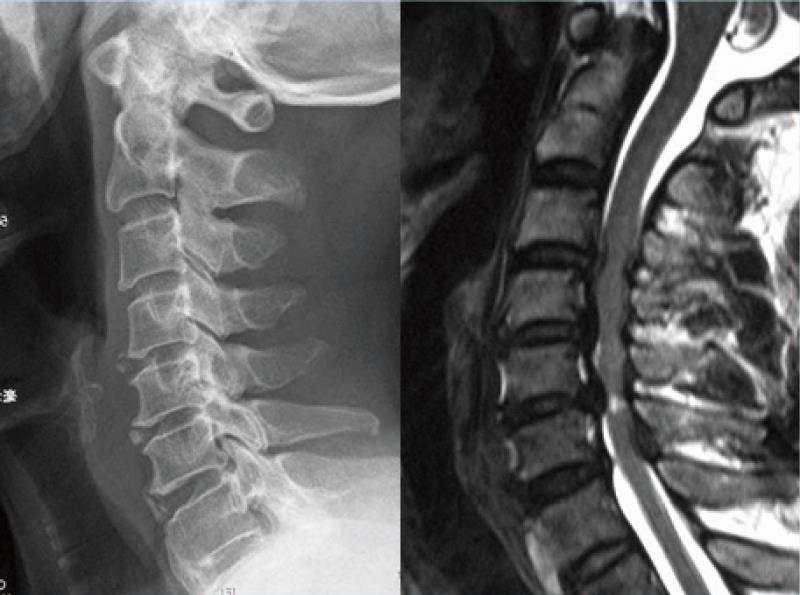

病例2 :颈椎后凸畸形矫形术

颈椎后凸畸形 颈椎前路C2-6椎间盘切除,后凸矫形术。术后随访示矫形效果满意。